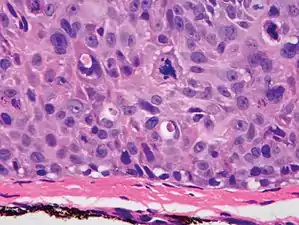

In invasive cSCC, tumor cells infiltrate through the basement membrane. The infiltrate can be somewhat difficult to detect in the early stages of invasion: however, additional indicators such as full thickness epidermal atypia and the involvement of hair follicles can be used to facilitate the diagnosis. Later stages of invasion are characterized by the formation of nests of atypical tumor cells in the dermis, often with a corresponding inflammatory infiltrate.[12]

Superficially invasive cutaneous squamous-cell carcinoma. These lesions often do not show the marked pleomorphism and atypical nuclei of cSCC in situ, but manifest early keratinocyte invasion of the dermis.[12]

High magnification demonstrates the pleomorphism of the invading keratinocytes[12]

Invasive nests with characteristic large celled centers. Ulceration (at left) is common in invasive cSCC.